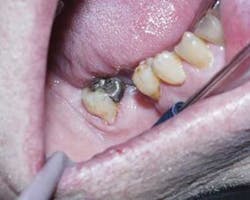

A 79-year-old male presented with an asymptomatic Class V carious lesion on Tooth No. 31. The following techniques were used:

1. Utilize direct access to the lesion without anesthesia (Figure 2).

3. Perform traditional preparation for composite. Starting in the center and top of the carious lesion, where the softest and most superficial decay was present, a gentle stroke motion similar to a brush stroke was applied (Figure 3) to each layer of infected dentin. An explorer and caries dye (Caries Finder, Danville) was used to remove the diseased dentin.